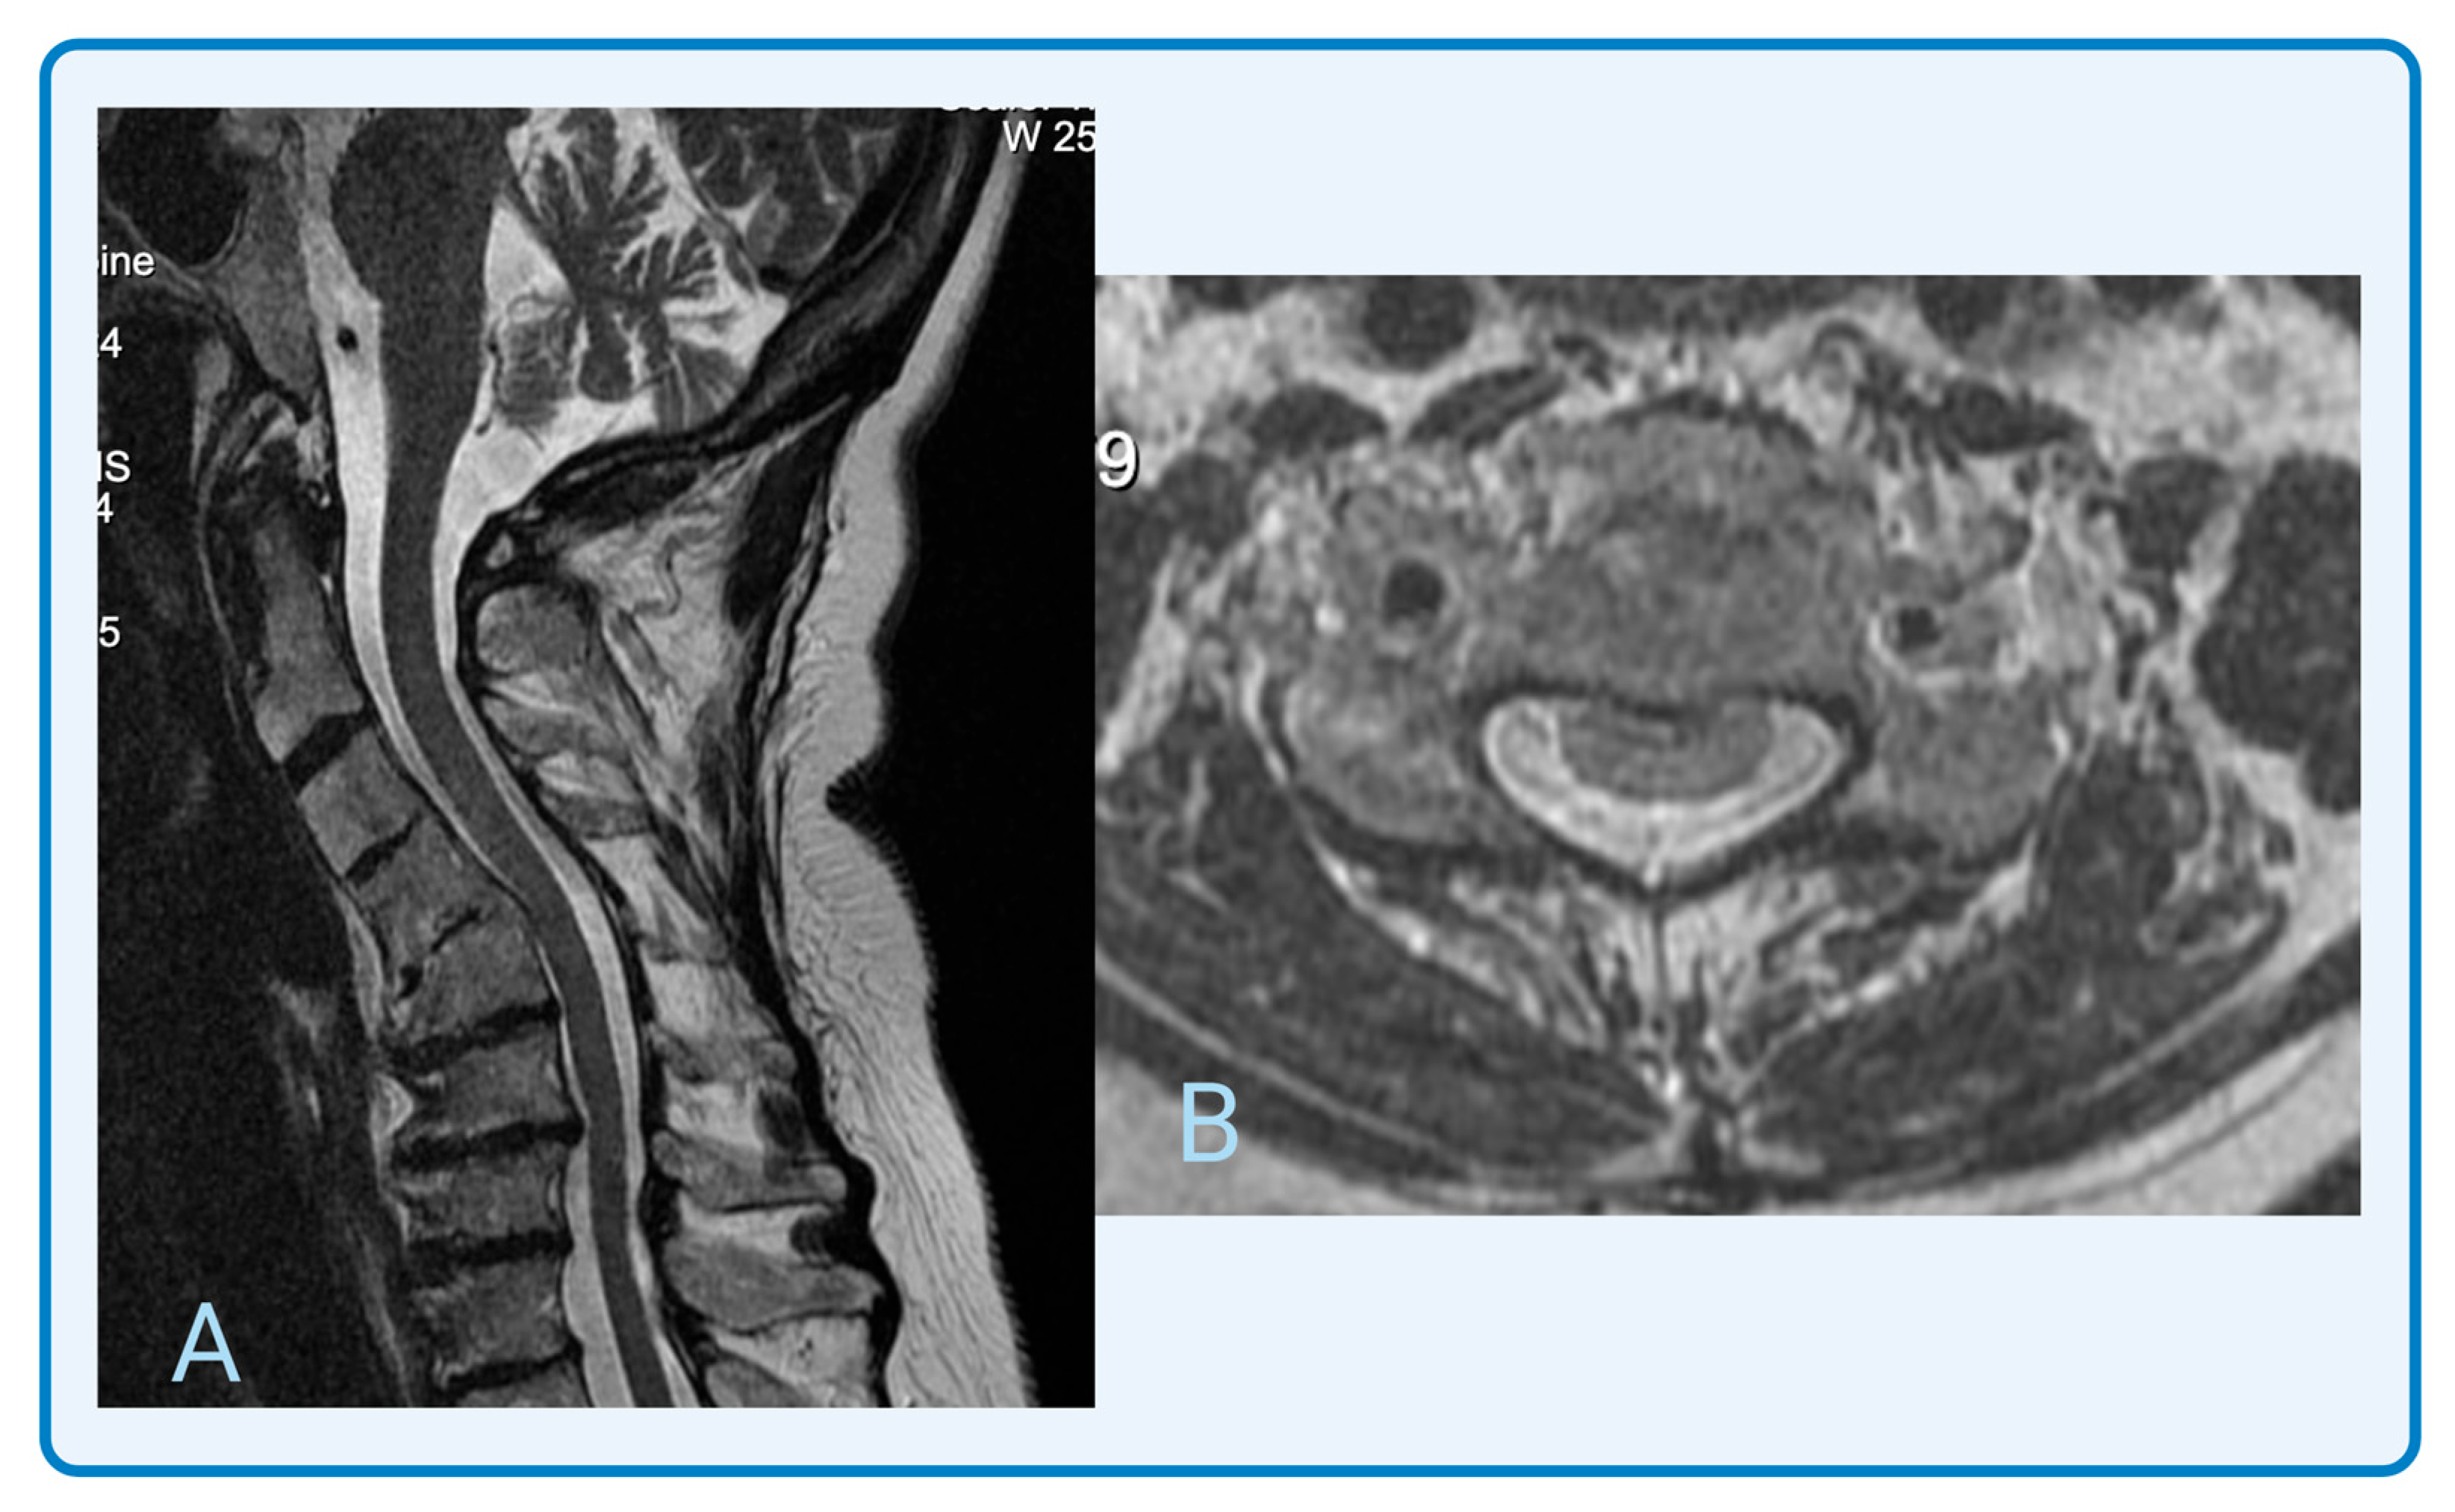

3.3. Radiographic Features of Degenerative Cervical Myelopathy